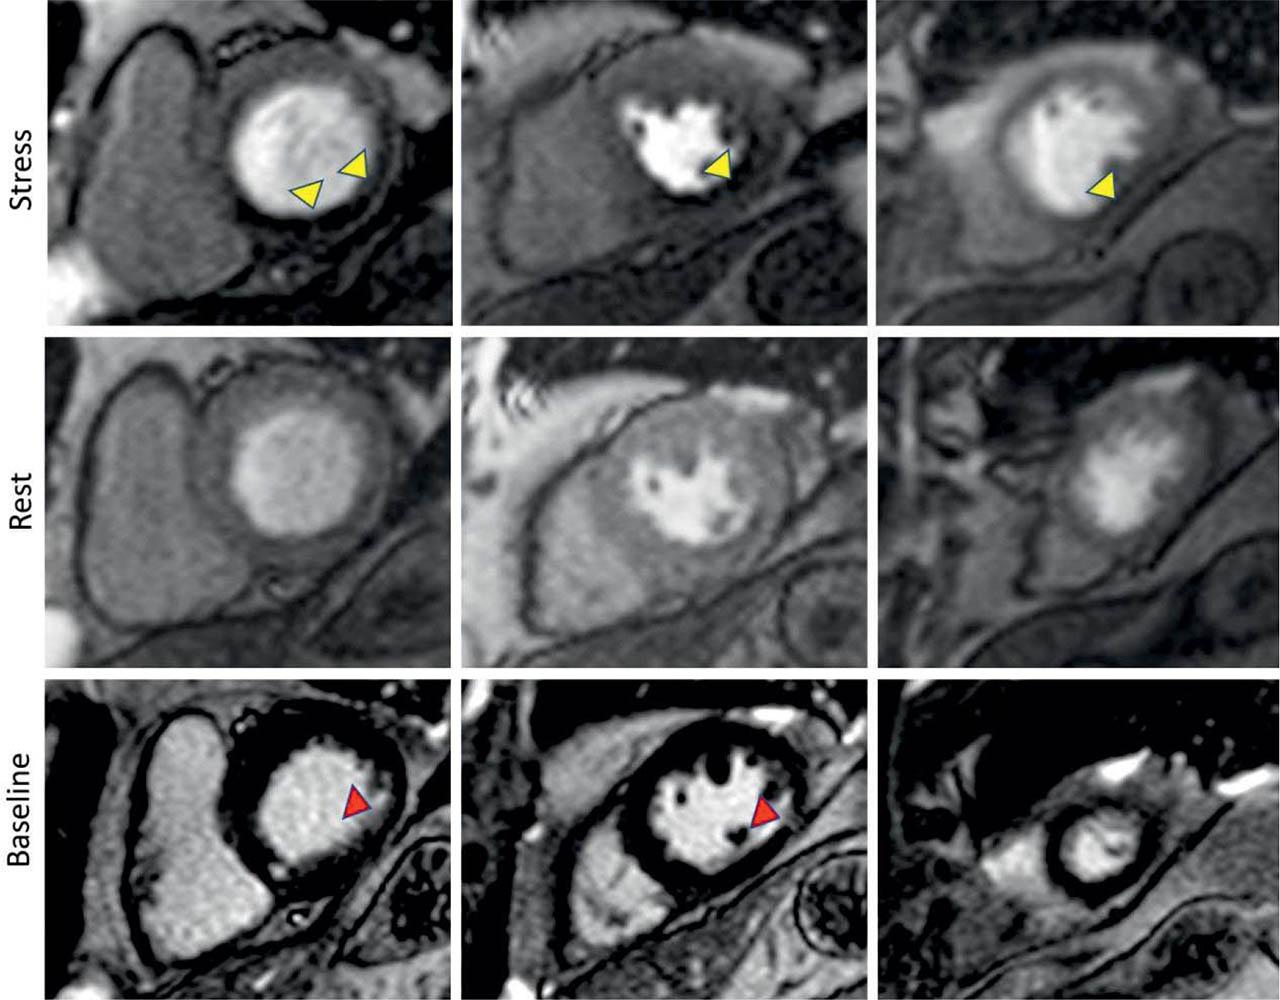

Figure 2